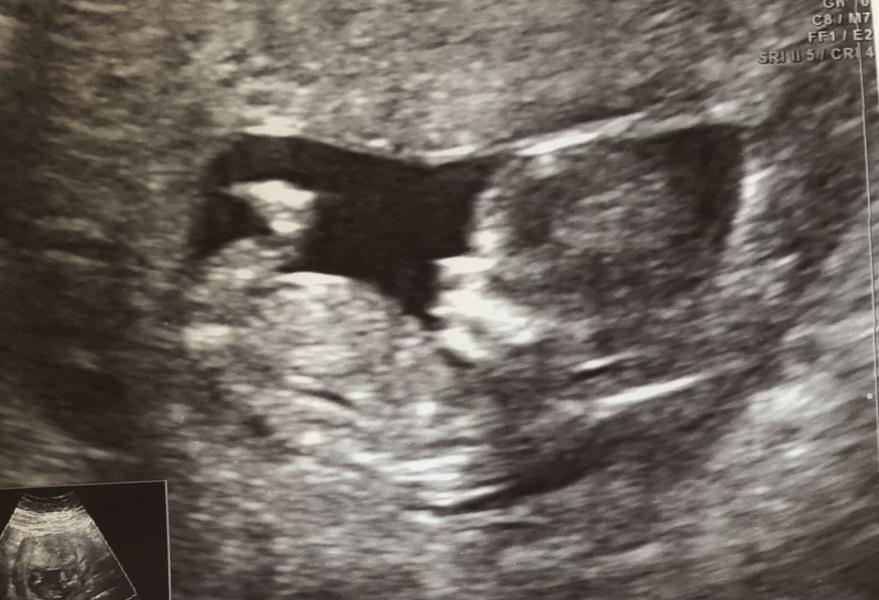

Пол не говорили,сердечко не включали послушать

На второй скрининг обязательно только платно пойду ,хочется вдвоём посмотреть на малыша

Пол видно без ошибочно только с 16 нед, мне вот предположили в 12 нед-не угадали))